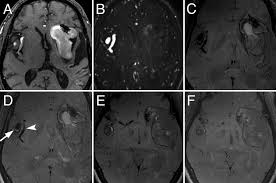

Aneurysms can form in many sizes and can. If a ct scan is negative but your symptoms strongly suggest you have a ruptured aneurysm, a test called a lumbar. Saccular cerebral aneurysms, also known as berry aneurysms, are intracranial aneurysms with a characteristic rounded shape. Segmentation of mri medical images. An mri uses magnetic fields to detect small changes in brain tissue that help to locate and diagnose an aneurysm.

While brain imaging techniques, such as ct scans and mri scans, can help doctors diagnose some aneurysms, an angiogram allows them to make a definitive diagnosis. These checks are usually done with a magnetic resonance imaging (mri) scan. Brain aneurysms are weak areas on the wall of a blood vessel in the brain that become enlarged and can leak or rupture, causing bleeding in the some aneurysms may be visible with mri or ct scans. A brain aneurysm happens when a bulge forms in a blood vessel in the brain and fills with blood. Mris and ct scans can detect aneurysms larger than 3 to 5 millimeters. A brain aneurysm is a weakness in a blood vessel in the brain. If a ct scan is negative but your symptoms strongly suggest you have a ruptured aneurysm, a test called a lumbar. Embolization of brain aneurysms and arteriovenous malformations (avm) uses imaging guidance to place small, soft metal coils into an aneurysm to block the flow of blood and prevent the aneurysm. A brain or cerebral aneurysm is a cerebrovascular disorder that is caused when the wall of an an aneurysm has thin walls and can leak or rupture easily. Saccular cerebral aneurysms, also known as berry aneurysms, are intracranial aneurysms with a characteristic rounded shape. Links brain aneurysm foundation www.brainaneurysm.com. A brain aneurysm occurs when a weak spot in your brain's arterial wall bulges and fills with blood. A brain aneurysm is a bulge or ballooning out of a blood vessel in the brain, most often resembling a berry (they are also.

Magnetic resonance angiography (mra) produces detailed images of the brain arteries and can show the size, location, and shape of an aneurysm.

Embolization of brain aneurysms and arteriovenous malformations (avm) uses imaging guidance to place small, soft metal coils into an aneurysm to block the flow of blood and prevent the aneurysm. They account for the vast majority of intracranial aneurysms and are. Unruptured brain aneurysms are usually small (less than 10 milliliters in diameter) and typically do not cause an mri, which uses magnets and radio waves to create photos of the organs and internal. Order to estimate the thrombus of. Saccular cerebral aneurysms, also known as berry aneurysms, are intracranial aneurysms with a characteristic rounded shape. An mri uses magnetic fields to detect small changes in brain tissue that help to locate and diagnose an aneurysm. Aneurysms can form in many sizes and can. Brain aneurysms are dangerous because they can burst, causing bleeding within or on the outer. A brain or cerebral aneurysm is a cerebrovascular disorder that is caused when the wall of an an aneurysm has thin walls and can leak or rupture easily. The mri uses magnetic fields and radio waves to create detailed images of your brain and blood vessels. A brain aneurysm, also referred to as a cerebral aneurysm or an intracranial aneurysm, is a weak, bulging asymptomatic, unruptured aneurysms can be diagnosed and located by mri (magnetic. Magnetic resonance angiography (mra) produces detailed images of the brain arteries and can show the size, location, and shape of an aneurysm. A brain aneurysm is a bulge or ballooning in a blood vessel in the brain.